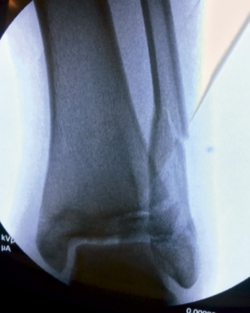

Se trata de un varón de 13 años de edad que acude a urgencias tras sufrir una caída y con eversión forzada del tobillo jugando al fútbol. A la exploración, presentaba inflamación en todo el tobillo izquierdo (región anterior y ambos maléolos) sin déficit neurovascular. En la radiografía simple se observó una fractura epifisiolisis de tipo IV (Figura 1).

Bajo anestesia general se intentó la reducción cerrada de las fracturas, sin éxito (Figura 3).

Figura 1. Radiografía: epifisiolisis de tipo IV asociada a fractura de tercio distal de peroné.

La radiografía simple muestra una fractura de tipo III de Salter y Harris en la proyección anteroposterior y una de tipo II en la lateral con fragmento metafisario posterior. Pueden existir fracturas de peroné asociadas en un 24-50% de los casos(3)(4). Se han descrito numerosas variaciones incluyendo 2, 3 y 4 fragmentos.